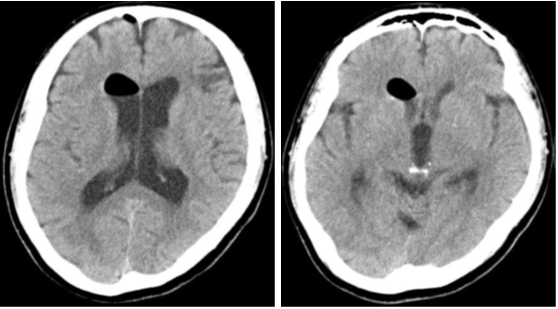

Figure 1 Noncontrast computed tomography showed a cyst in the pineal region with ventriculomegaly.

A 52-year-old man with a headache and consciousness disturbance was taken to our hospital by ambulance. He had a history of thrombocythemia and was taking aspirin. At the time of the visit, his consciousness was GCSE4V4M6, and displayed an upward gaze disorder. Computed tomography (CT) at the first visit revealed ventricular enlargement and a cyst with calcification in the pineal gland. Additionally, ventricular enlargement was visible on MRI, and a pineal gland cystic lesion with a wall thickness of 15 mm was discovered. The signal inside the cyst was lower than that of the surrounding brain parenchyma and higher than that of the cerebrospinal fluid. The cyst wall was thin and smooth, and no septal structure or nodules were discovered inside, so we diagnosed a pineal cyst. The operation was performed under general anesthesia, trepanned on the right frontal mid-pupillary line and in front of the coronal suture, and a transparent sheath was placed and a flexible scope was inserted. The cerebral aqueduct intermittently became blocked as the cyst floated in time with the cerebrospinal fluid flow. With forceps, the cyst wall was ruptured, releasing a fluid with a pale yellowish serous content. When about half of the cyst wall was removed, it was validated that the cyst had originated from the pineal gland, and the cerebral aqueduct became observable, so we decided to finish the cyst wall removal. Furthermore, we conducted an endoscopic third ventriculostomy, and pulsatile movement of the third ventricular floor was observed. The operation improved the ocular motility disorder and consciousness disorder, and the ventricles shrank on CT. Postoperative MRI revealed that the cyst wall was discontinuous, and the stoma of the third ventricle was also verified. After the surgery, the postoperative course was uneventful and he was discharged on the 8th postoperative day without complications. Ventriculomegaly was not found. on MRI six months after the operation.